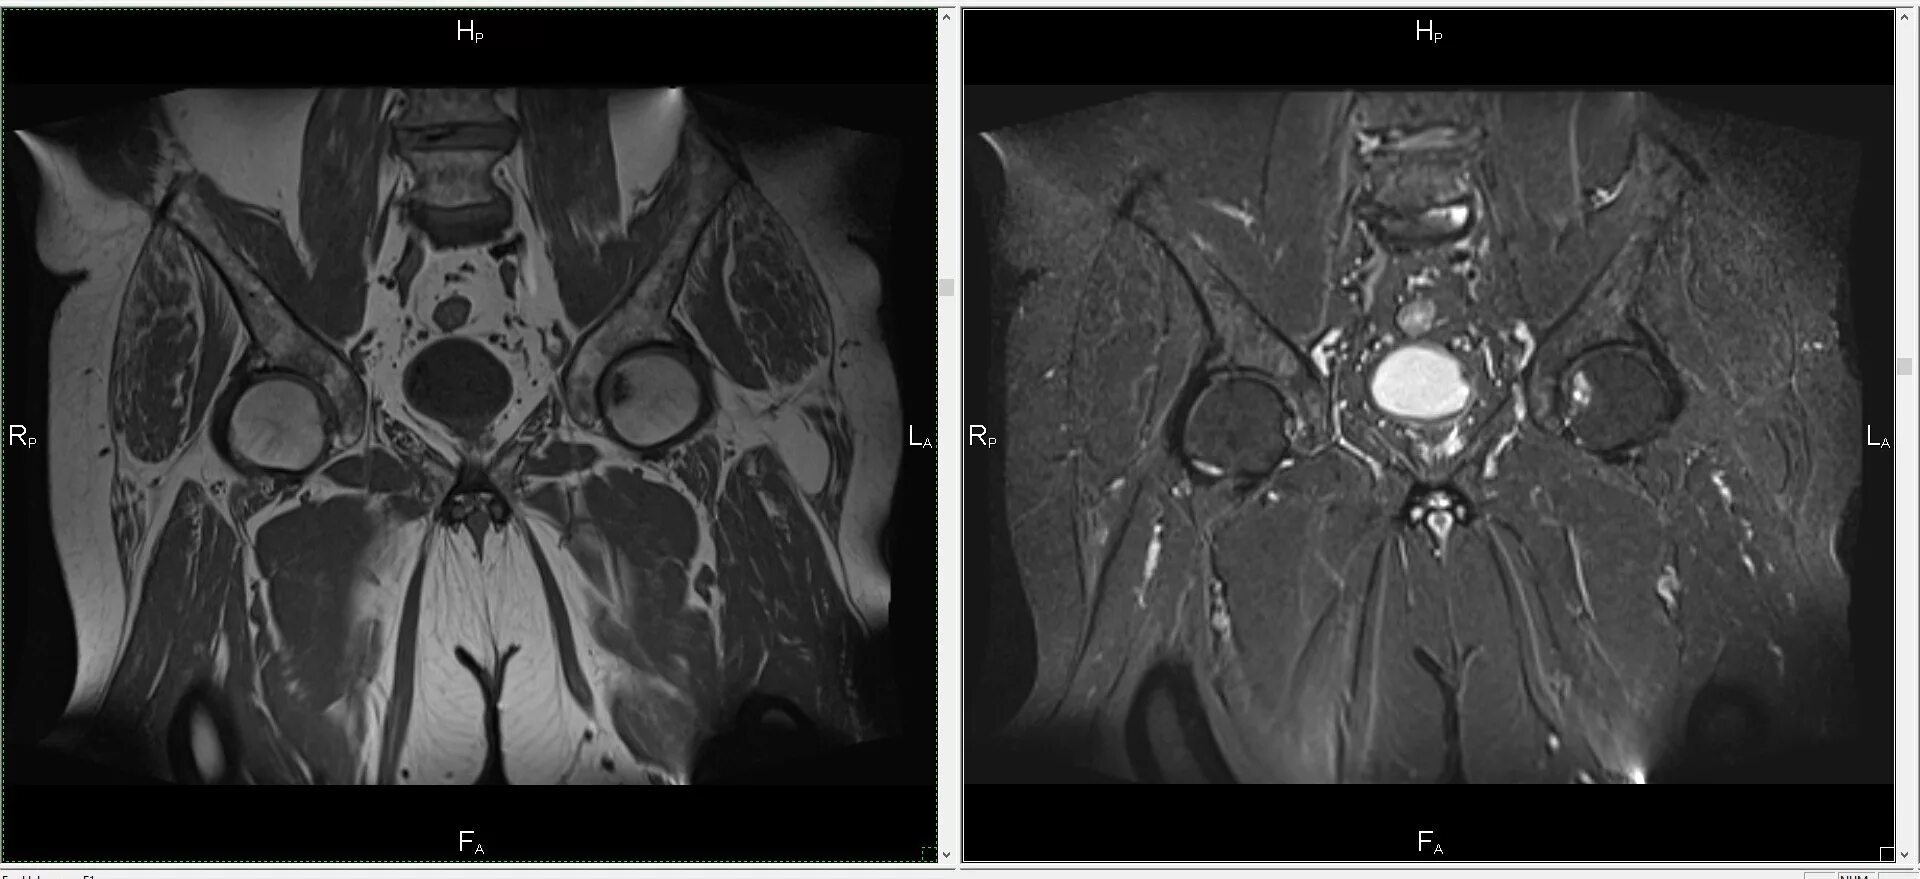

Мрт или кт тазобедренных суставов что лучше